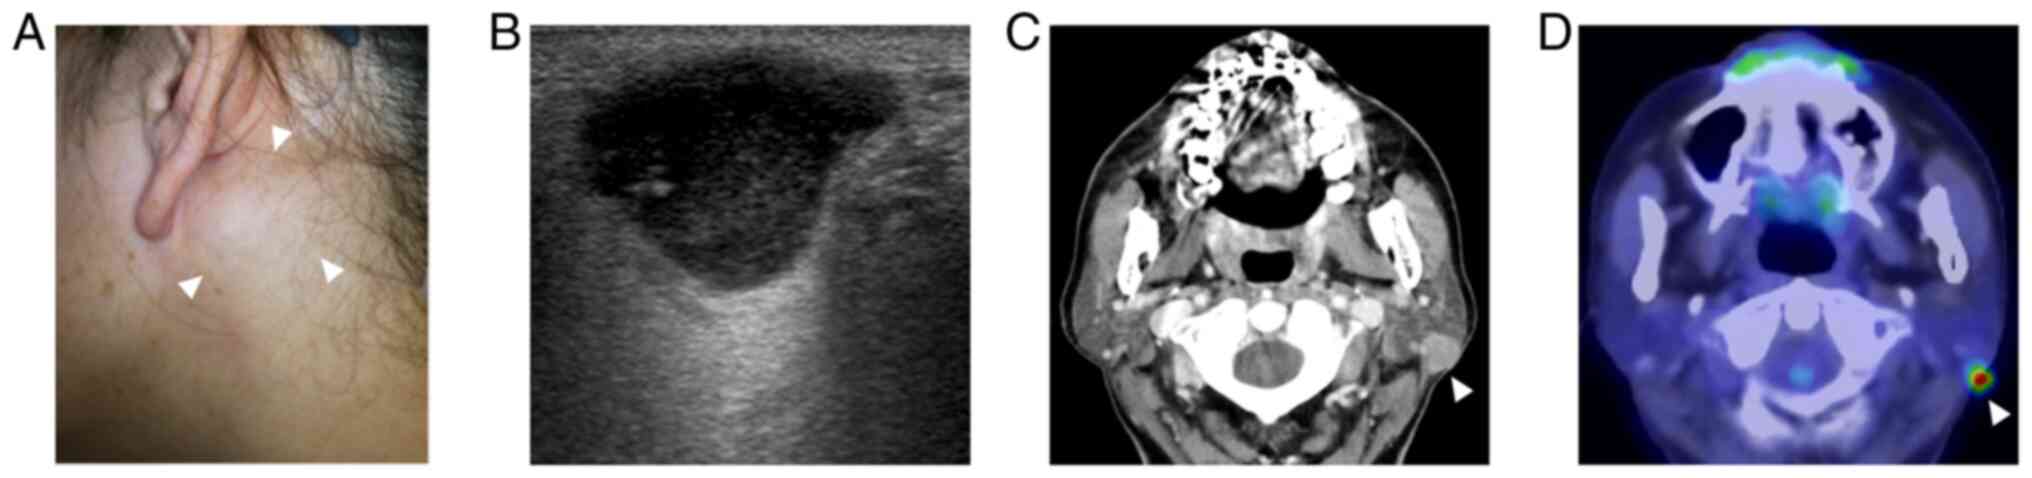

A 60-year-old Japanese woman with a 3-years history of a slow-growing, painless mass in her left parotid gland was admitted to our department. She had no medical or familial history of note. A thumb-sized, hard mass was palpated on the left parotid gland (Fig. 1A). No facial palsy was observed. Endoscopic examination did not reveal any tumorous lesions in the nasopharynx. Ultrasonography revealed a well-circumscribed, lobulated, hypoechoic mass with posterior enhancement measuring 19x12x10 mm in the left parotid gland (Fig. 1B). Computed tomography (CT) revealed a well-circumscribed, solid mass exhibiting homogeneous enhancement in the posterior part of the left parotid gland (Fig. 1C). No abnormal enlargement of lymph nodes was identified. Fluorodeoxyglucose-positron emission tomography (FDG-PET)/CT revealed uptake by the tumor, but not in other areas including the nasopharynx (Fig. 1D). Fine-needle aspiration cytology (FNAC) demonstrated numerous irregularly shaped trabecular clusters of relatively large cancer cells with vesicular chromatin and prominent ‘cherry-red’ nucleoli (Fig. 2A). Lymphocytic infiltrate was not conspicuous. Cytologically, poorly differentiated carcinoma was suggested. The patient underwent left superficial parotidectomy with adequate safety margins. After making an S-shaped incision, the facial nerve was identified and preserved. The adjacent portion of the sternocleidomastoid muscle was resected, and selective neck dissection of Level II was added. Her clinical course proved uneventful. Postoperatively, the patient received radiotherapy to the parotid gland area at 50 Gy and then has been screened with ultrasonography and CT scan at fixed intervals. No evidence of recurrence has been observed as of 20 months postoperatively.

Ultrasonographically, LEC lesions have been described as a hypoechoic solid mass with posterior enhancement and increased vascularity on color Doppler images (12). On CT scan, the lesions have been depicted as exophytic, solid masses with good contrast enhancement in the parotid gland (12). Fifteen of 27 patients (56%) with EBV-associated LEC revealed neck lymph node metastasis (Table I). Identification of enlarged lymph nodes by imaging studies should merit consideration of neck lymph node dissection.

Histologically, LEC consists of infiltrative sheets, islands and cords of cancer cells that are separated by dense lymphoid stroma. The tumor cells are characterized by indistinct cell borders (i.e., syncytial), lightly eosinophilic cytoplasm, oval moderately pleomorphic vesicular nuclei with conspicuous nucleoli (1). Immunohistochemical examination is of great help in the diagnosis of LEC. Epithelial markers such as AE1/AE3 highlight cancer cells that might be markedly obscured by densely infiltrating lymphocytes and plasma cells. The main differential includes metastasis from either NPC or lymphoepithelial-like carcinoma arising in other organs (e.g., stomach) to not only parotid parenchyma but also to intraglandular lymph node. In the present case, endoscopic examination of the nasopharynx and FDG-PET/CT excluded metastasis.